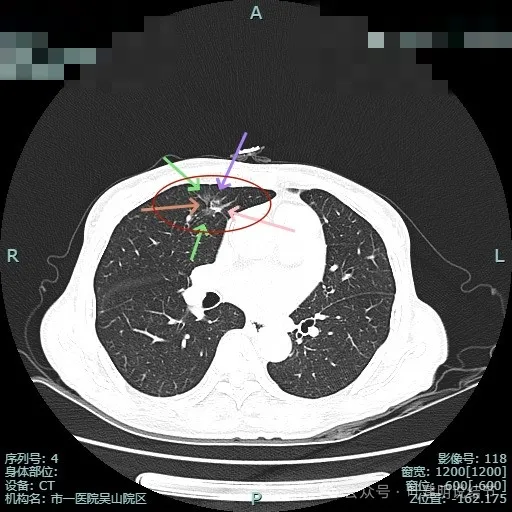

先来看2024年6月某省级医院的影像:‘

这个病灶是混合密度,边缘毛糙有细毛刺,毛刺较锐利,灶内有细支气管通气征,整体轮廓较清。如果之前也有在的,则基本上肯定是肺癌,而且至少是微浸润性腺癌。